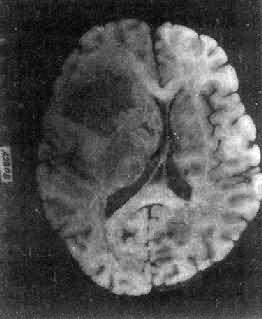

肉眼观,肿瘤为数厘米的结节至巨大块状。分化较好的肿瘤,境界不清;而分化程度较低的肿瘤则境界分明。瘤体灰白色。质地视肿瘤内胶质纤维多少而异,或硬、或软、或呈胶冻状外观,并可形成大小不等的囊腔。由于肿瘤的生长、占位和邻近脑细胞的肿胀,脑的原有结构因受挤压而扭曲变形(图16-23)。

图16-23 星形胶质细胞瘤

左大脑半球肿胀,肿瘤边界不清,部分呈胶冻状

高度恶性的星形胶质细胞瘤称为多形性胶质母细胞瘤(glioblastoma multiforme),多见于成人。肿瘤好发于额叶、颞叶白质,浸润范围广,常可穿过胼胝体到对侧,呈蝴蝶状生长(图16-24)。瘤体因常有出血坏死而呈红褐色。镜下,细胞密集,异型性明显,可见怪异的单核或多核瘤巨细胞。出血坏死明显,是其区别于间变性星形胶质细胞瘤的特征。毛细血管明显增生,内皮细胞增生、肿大,可导致管腔闭塞和血栓形成。肿瘤发展迅速,预后极差,患者多在2年内死亡。